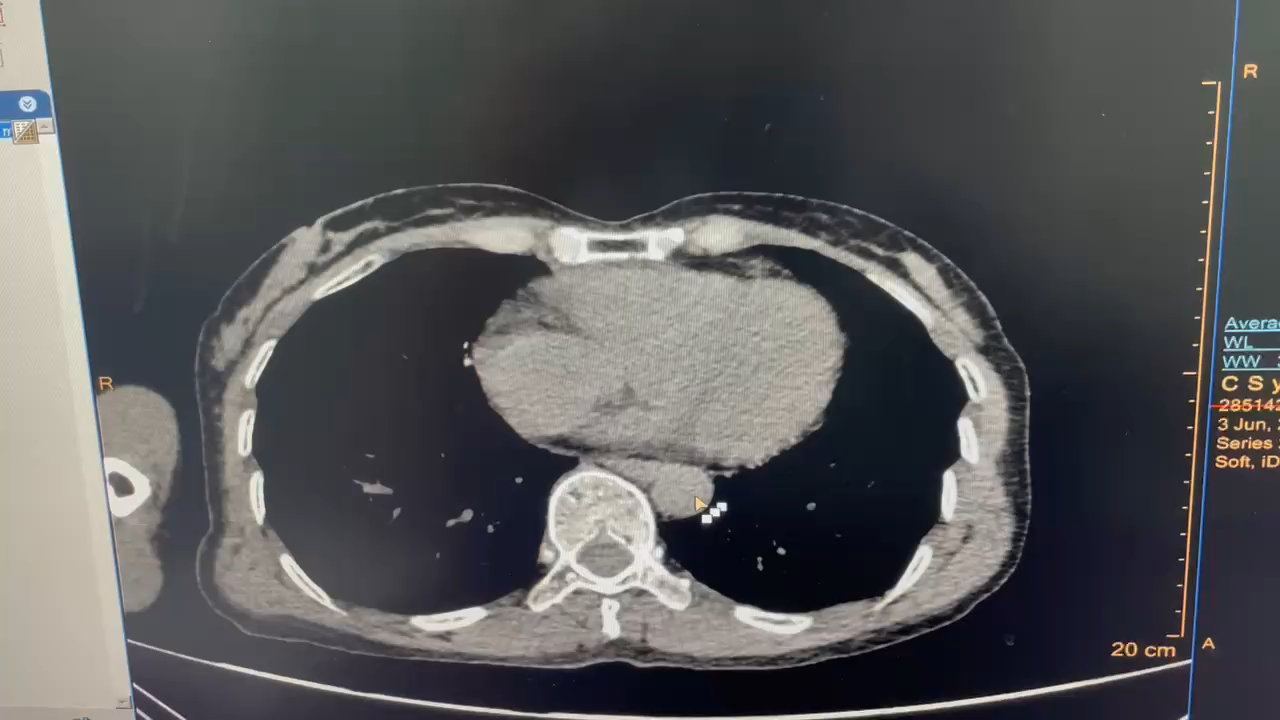

【检查】:颅脑CT平扫、胸部CT平扫、上腹部CT平扫、下腹部CT平扫、颈椎CT平扫(C4-C7椎体)、颈椎CT平扫(C1-C3椎体)提示: 1、左侧少量气胸,左肺受压约5%;双肺下叶絮状影,挫伤可能;右肺中叶、左肺上叶条索状密度增高影,纤维增殖灶?挫伤?请结合临床。2、双肺下叶结节影,Lung-RADS 2级,建议1年复查。右肺上叶钙化灶。3、左侧肩胛骨骨折;左侧第5、9、10肋骨骨折。4、左侧第4、6、8、12肋骨骨折可疑;右侧第4肋骨陈旧骨折;请结合临床。5、左肾体积稍大、密度欠均匀,肾挫伤可疑;左肾包膜下血肿;请结合临床。6、左侧肾上腺区类圆形稍高密度影,外伤性改变?其他?建议增强。7、左中腹腔、双下腹腔少许条絮状密度增高影,考虑外伤性改变,请结合临床。8、右肾多发结石(较大者约10×9mm)伴轻度积水。9、子宫稍高密度影可疑,请结合临床及超声除外病灶。10、盆腔小片状密度增高影,积血?肠管影?请结合临床及复查。11、左侧髂骨及耻骨联合、右侧骶骨翼及耻骨下支骨折。12、右侧耻骨上支、L5左侧下关节突骨折可疑,请结合临床。13、腹主动脉、髂动脉硬化。胸腰椎退变。14左髂部软组织挫伤。15、颅脑未见明显外伤性异常。16、颈椎退变伴轻度反弓。项韧带钙化。17、附见双侧下鼻甲肥大。我院急诊绿色通道 左侧肱骨正侧位片+左侧肘关节正侧位片+右侧股骨正侧位片+右侧膝关节正侧位片+云影像 提示:1、左侧肱骨中段骨折伴周围软组织稍肿胀。2、右侧膝关节、左侧肘关节、右侧股骨未见明确骨折征象。必要时 建议CT除外细微骨折。

【临床诊断】: 1、左肾挫裂伤;2.左侧创伤性气胸;3.左侧多发肋骨骨折;4.双肺挫伤;5.左侧肩胛骨骨折;6.左侧髂骨骨折;7.耻骨联合骨折;8.右侧骶骨翼骨折;9.右侧耻骨下支骨折;10. 左侧肱骨中段骨折伴周围软组织稍肿胀;11.左侧第4、6、8、12肋骨骨折?

考虑肾脏挫裂伤所致,且患者血压降低(95/58mmhg),若出血进一步加重,出现失血性休克,危及生命可能,需进一步止血治疗,因患者右肾萎缩、合并右肾结石并积水,开放手术修补困难,若修补失败需要行左肾切除术,故建议行高选择左肾动脉介入栓塞术。当日急诊介入科行超选择肾动脉栓塞术,术后血尿明显好转;经治疗后复查肾出血控制,血色素无下降。拟待患者病情好转后转入骨科进一步手术治疗。

经超滑导丝引入YASHIRO导管钩挂左侧肾动脉成功后经高压注射造影剂减影,见左肾动脉上部分支走形形态正常,未见明显造影剂滞留及外溢现象,左肾动脉下部一分支见细小分支不清,见少许造影剂外溢,逐引入微导丝、微导管(MC-PE27131)超选择该分支动脉,后手推减影见假性动脉瘤,并可见造影剂外溢,逐以350-560um明胶海绵颗粒悬液行动脉栓塞,复查造影栓塞可,退管。经超滑导丝引入YASHIRO导管钩挂右肾动脉成功后经高压注射造影剂减影,见其各个分支未见明显出血征象,未见造影剂滞留及外溢。后退管更换COBRA导管于腹主动脉成袢后引入左侧髂内动脉、臀上动脉手推减影示,各分支未见明显出血征象,未见造影剂滞留及外溢。